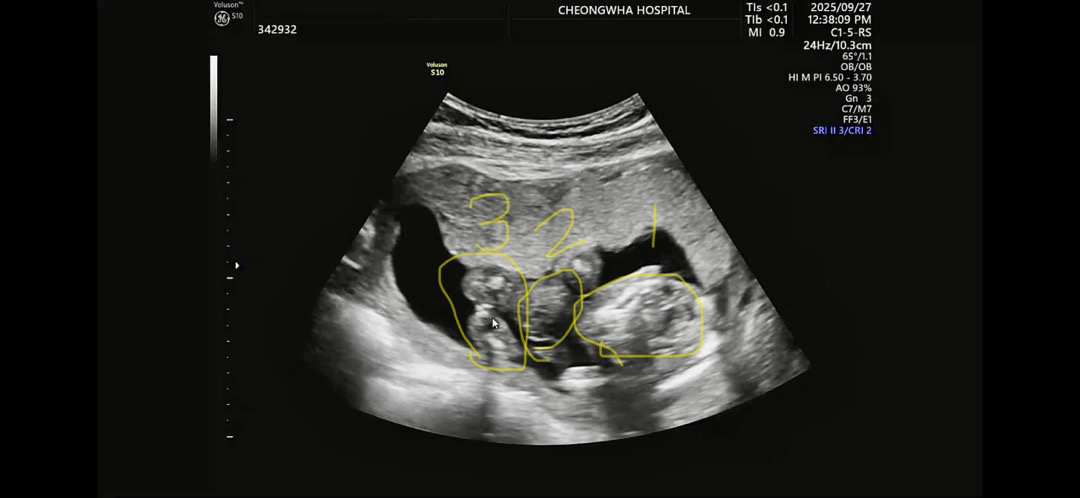

오른쪽부터 머리 몸 다리 순서인데 아들일까요 딸일까요 -?!

결과는 .... 딸입니다.ㅎ